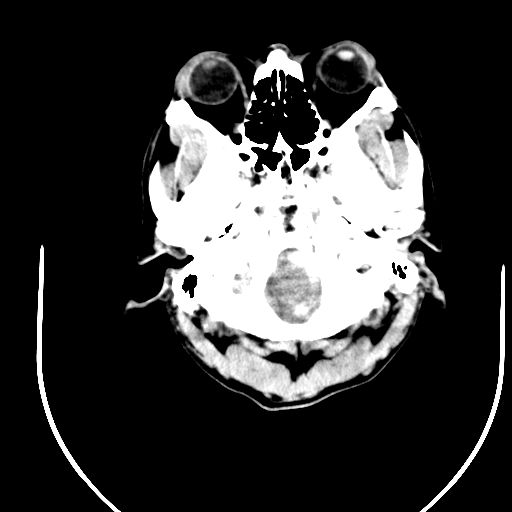

标题: CT24997:M,60Y,突发昏迷30分钟,有高血压病史。 [打印本页]

标题: CT24997:M,60Y,突发昏迷30分钟,有高血压病史。

右侧基底节区脑出血并破溃入脑室。

1右侧基底节脑出血伴脑干出血并破入脑室系统脑疝形成2梗阻性脑积水

1)右侧基底节脑出血伴脑干出血并破入脑室系统。2)大脑镰下疝。3)梗阻性脑积水。